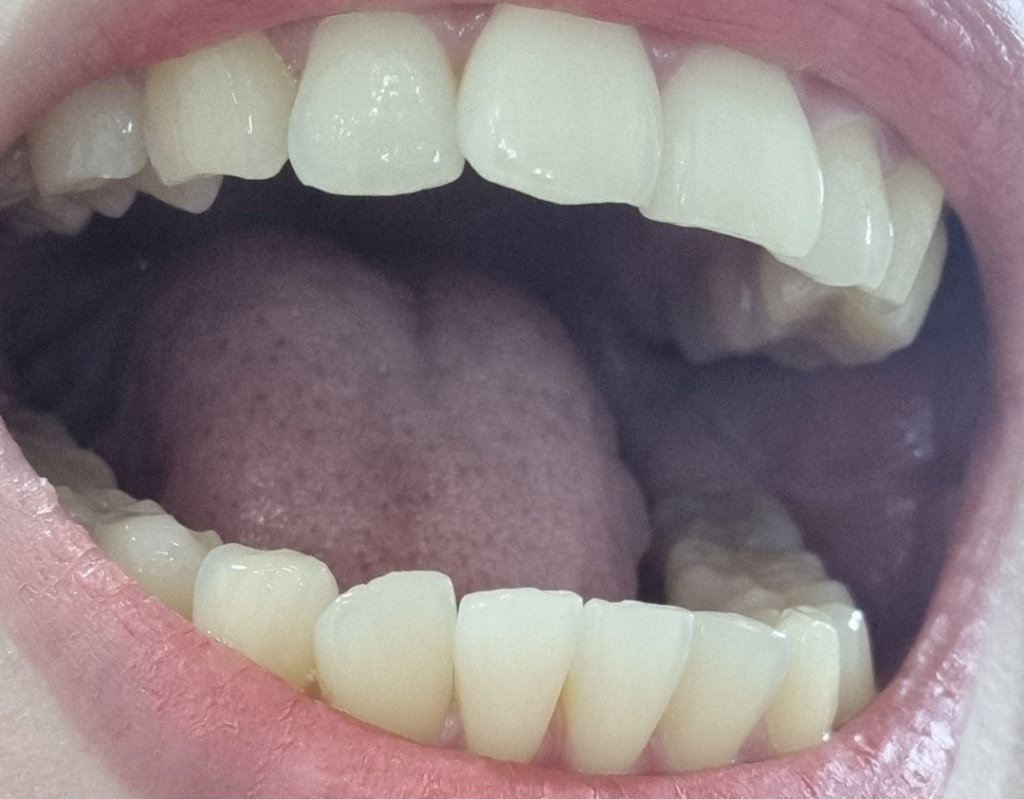

치아마모가 심한편인가요? 관리를 어떻게 해야할까요?

치아에 실금도 많다고 하시고 혀로 만져보면 까끌까끌 금간게 느껴집니다.

1. 치아 마모가 심각한 수준일까요?

• 4번 째 사진

사진상으로 보면 치아 마모상태가 심한거 같진 않습니다. 턱관절이 아프거나 그럴경우에는 스플린트나 보톡스 치료를 받으시면될것같습니다.

1. 사진상 치아 마모가 아주 심한 수준은 아니라고 판단됩니다.